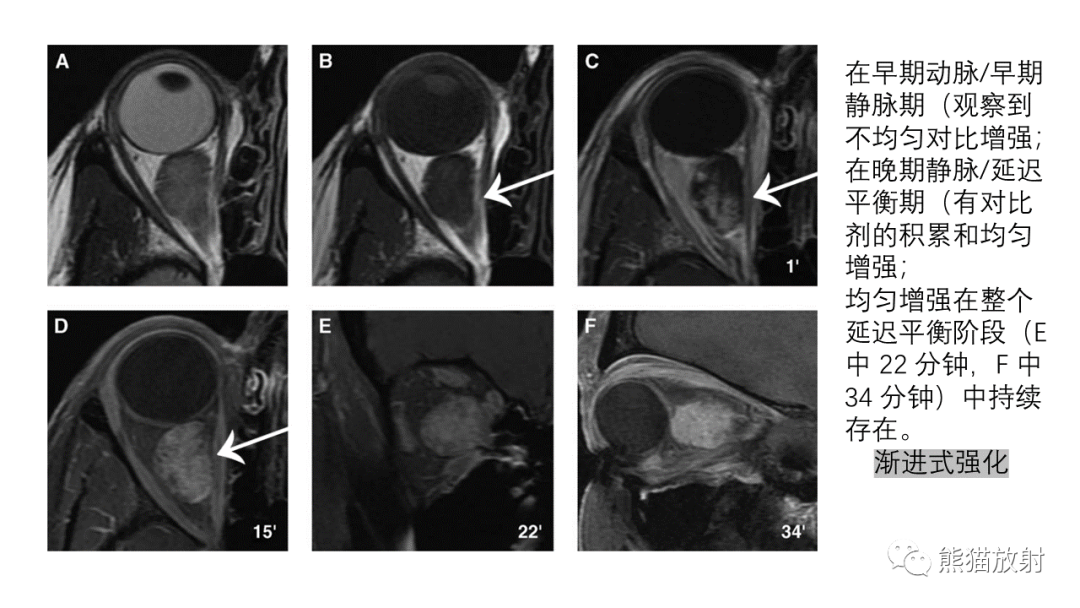

【PPT】泪腺多形性腺瘤 VS 眼眶淋巴瘤-2